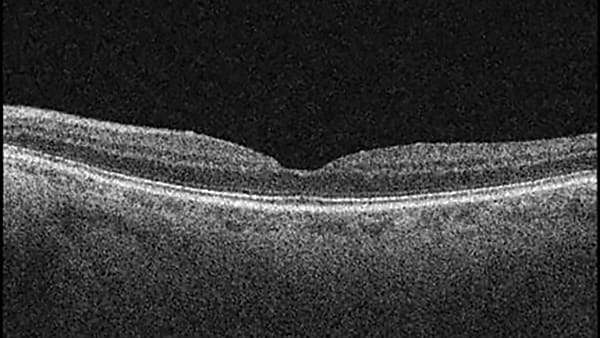

A Case of Cystoid Macular Edema Associated With Maintenance-dose Ozanimod

This case report will discuss asymptomatic CME in the maintenance period of ozanimod use for moderate to severe ulcerative colitis.

By Jeffrey Bloom, DO, Caleb Liles, DO, Jacob Brucker, DO, et al.